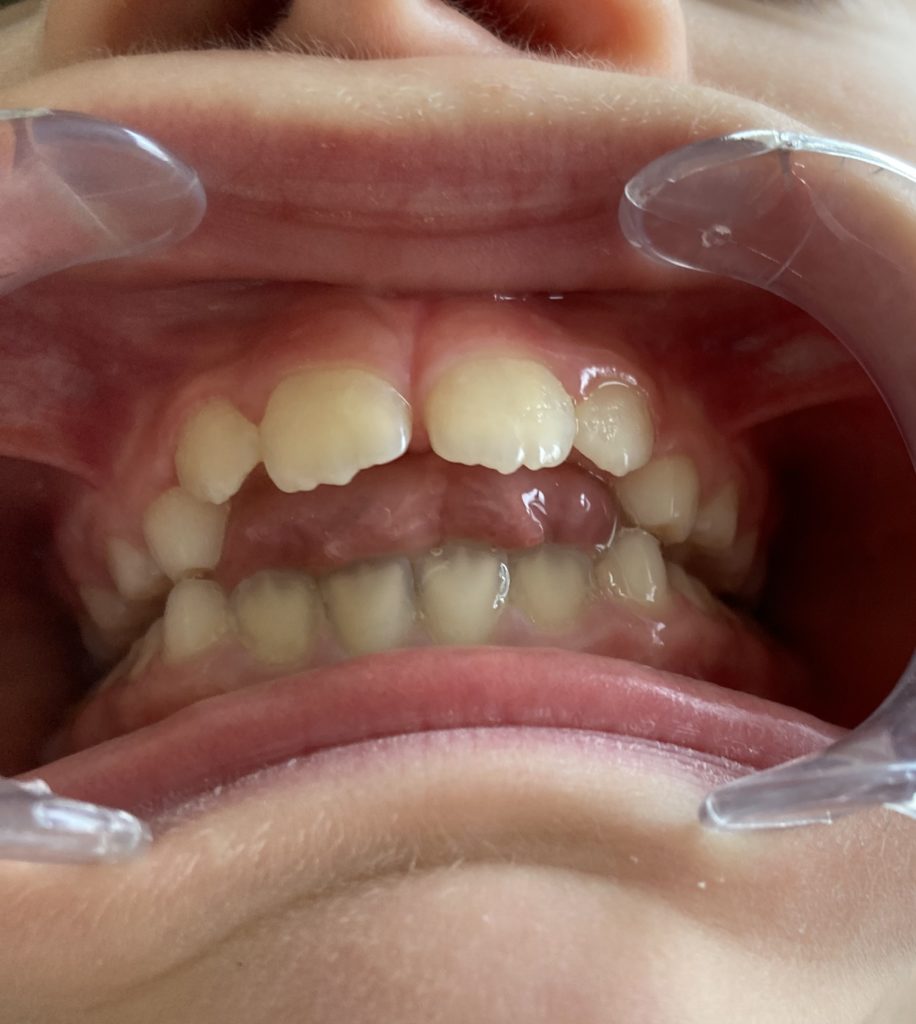

Découvrez en images l’évolution d’une béance liée à une dyspraxie linguale et les bénéfices apportés par une prise en charge adaptée.